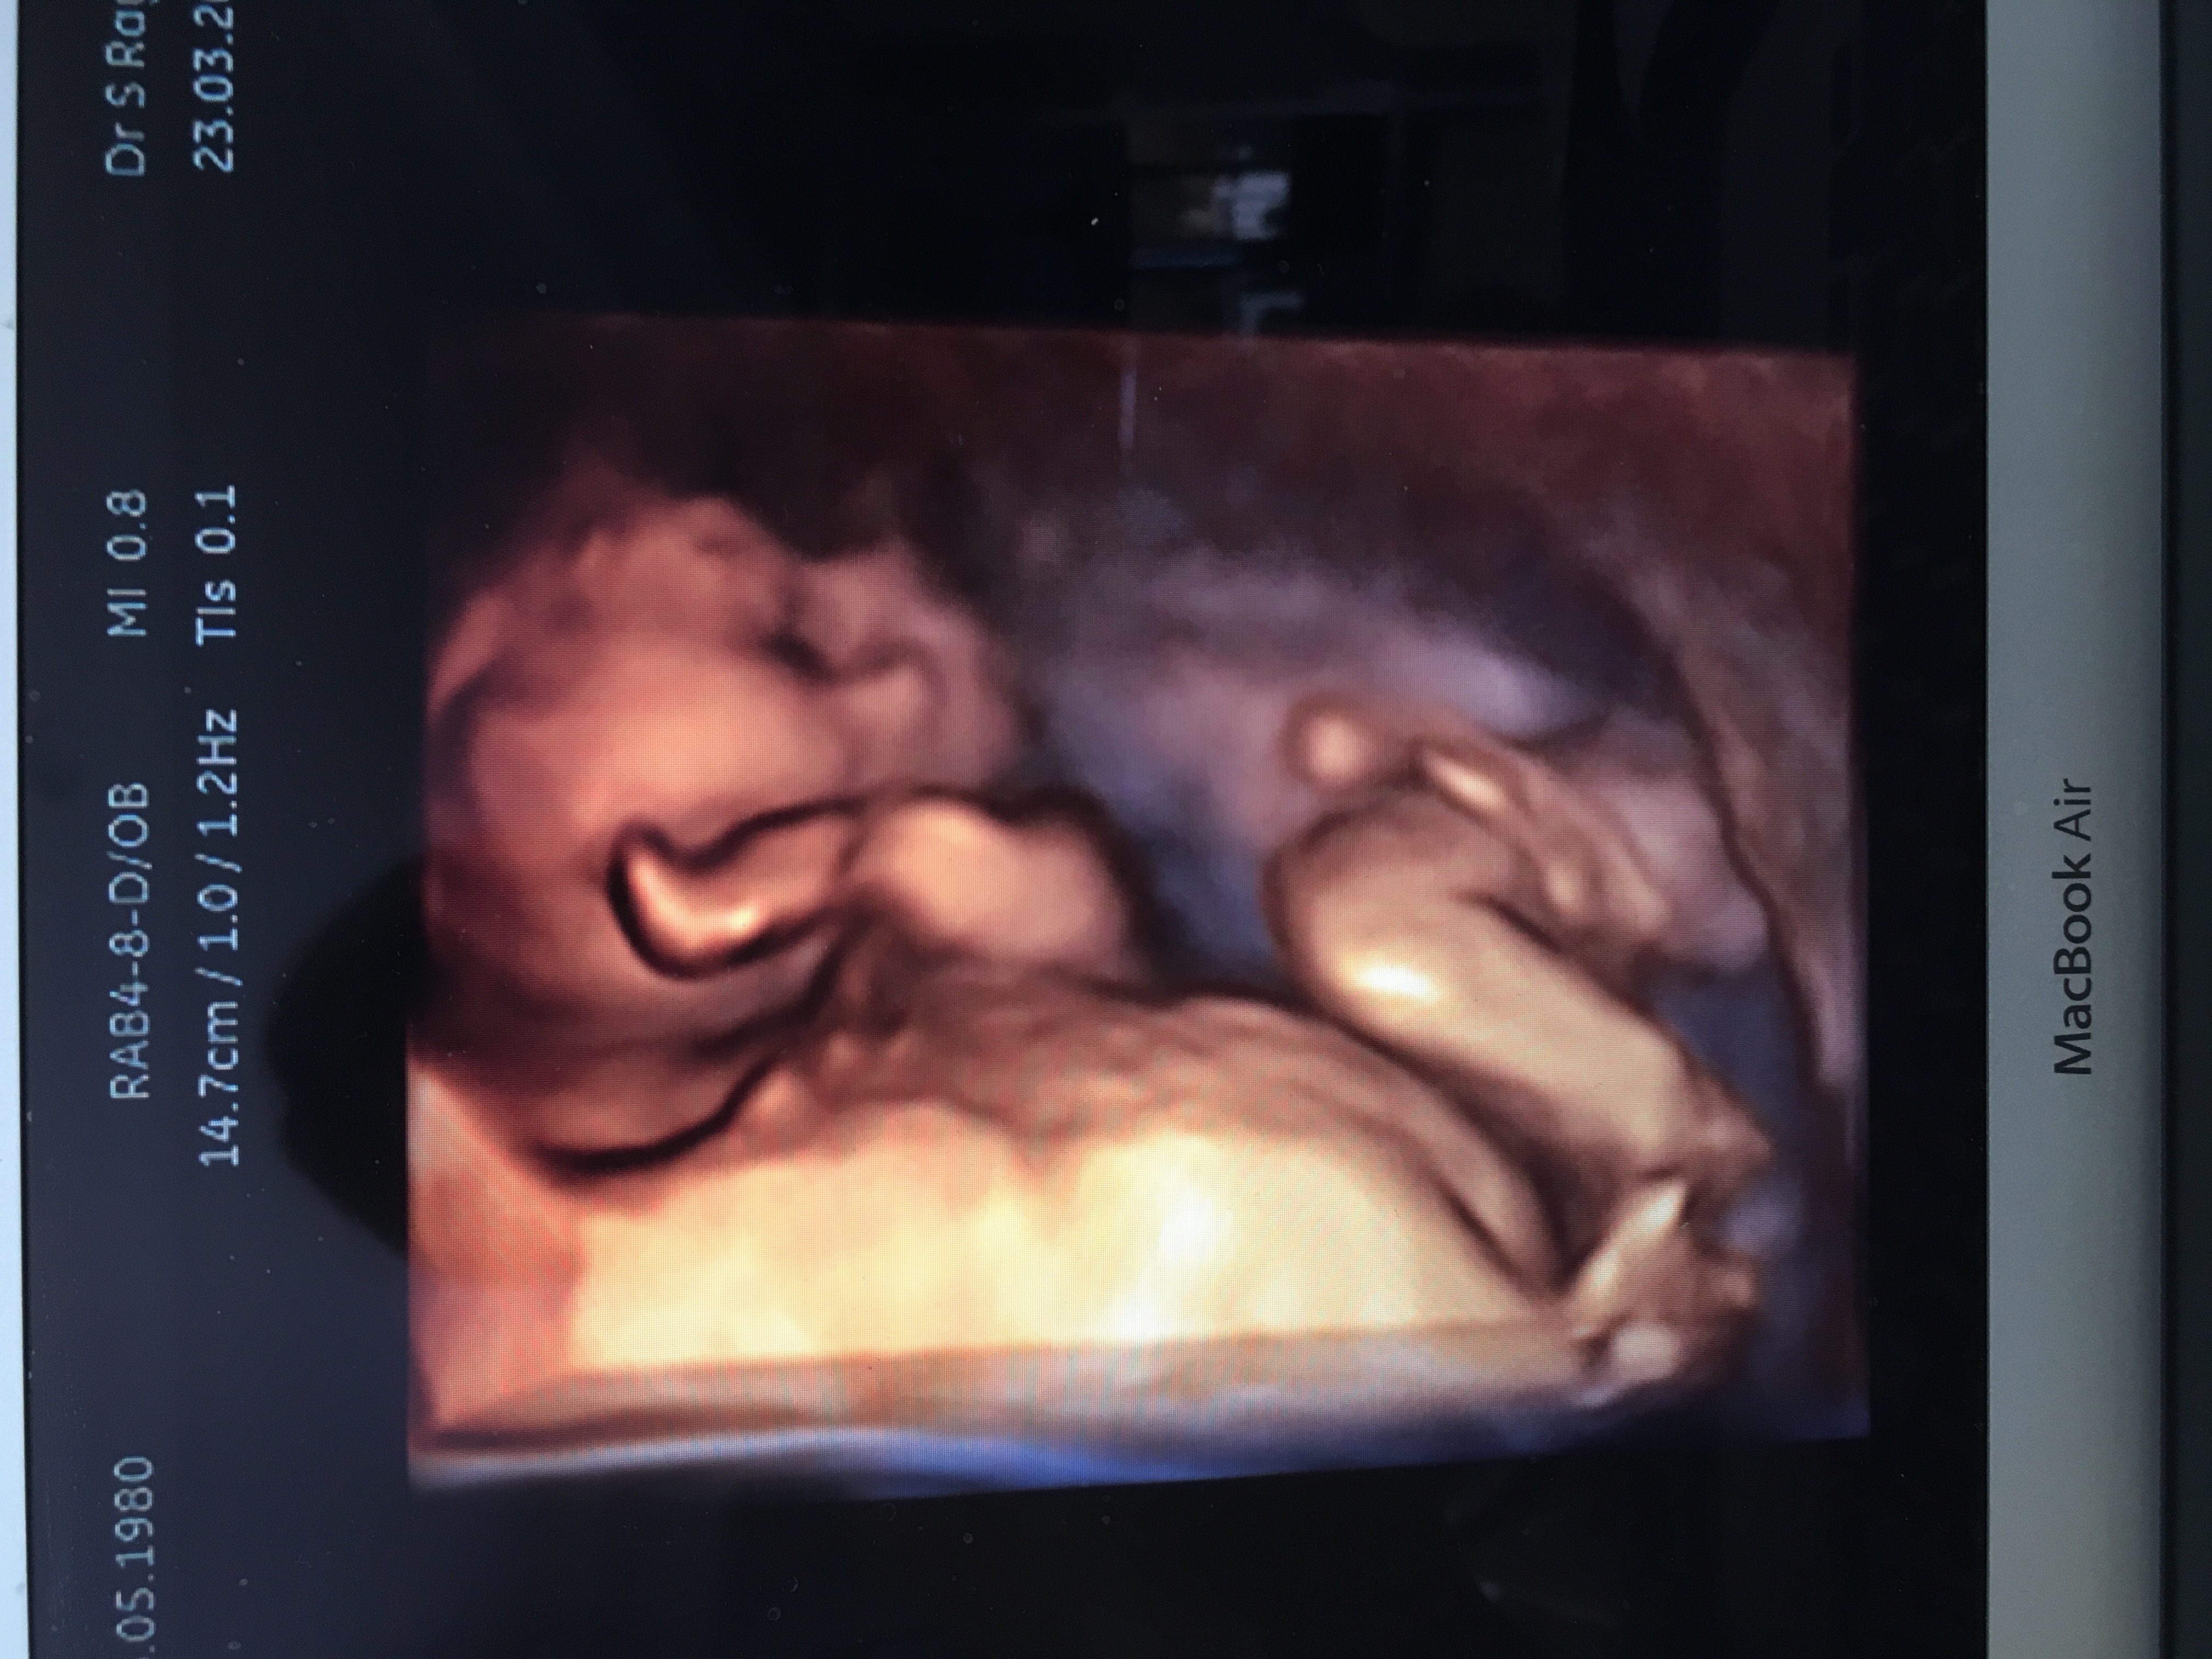

What do you think? Sonographer said confidently boy but I can see lines and think it could be swollen labia? Cord is also around baby's legs as you can see in 4d pic. Attachment 35555Attachment 35556Attachment 35557